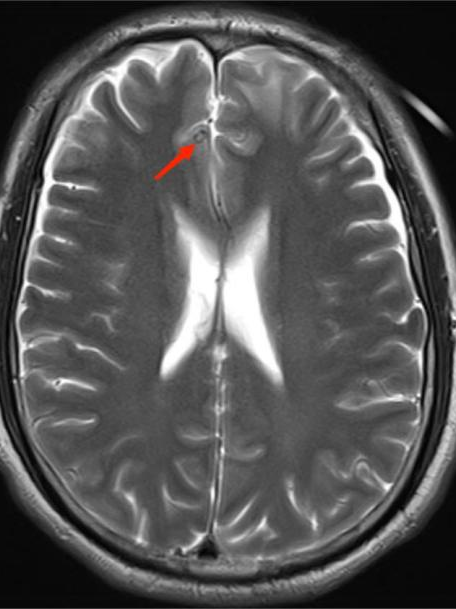

得到这条线索后,ICU 医生立即为李先生进行一系列脑部检查。最终,李先生头颅 MR 显示其脑内有寄生虫感染!明确诊断为脑囊虫病!